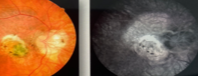

Paciente masculino, 8 anos, apresenta redução da acuidade visual somente no olho direito, há cerca de 2 meses.

Trata-se da doença de Coats, caracterizada por telangiectasias, microaneurismas e exsudação. É mais comum em homens com menos de 10 anos de idade e frequentemente é unilateral.

A fotocoagulação deve ser feita nas áreas de não perfusão para reduzir o risco de neovascularização e favorecer a reabsorção dos exsudatos.